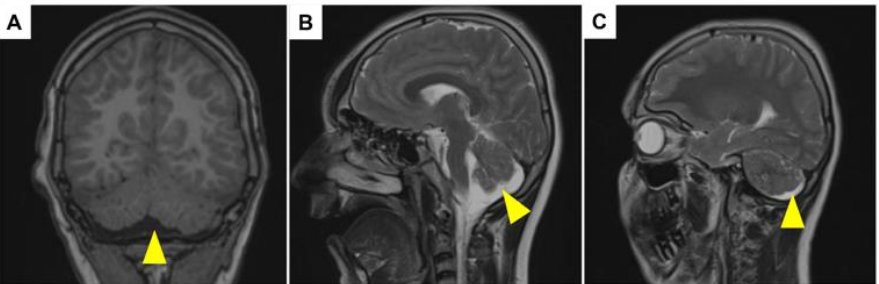

Sibling 3: A 19-year-old male patient, the last child of the family, who has a neuromotor developmental delay like his siblings, and has milder symptoms than his siblings. He started walking after the age of 3 and can express himself, albeit slightly. He has a history of febrile seizures at the age of 1 year, his EEG was found to be within normal limits, and he is being followed up by Pediatric Psychiatry due to his hyperactivity. On neurological examination, muscle strength was 4/5 in the upper extremity, no DTR was obtained, +4/5 in the lower extremity, DTR was hypoactive, slightly ataxic, and there was incompetence in cerebellar tests. Creatine kinase values were found to be high, and there was cerebellar atrophy in the patient's cranial MRI (Figure 2). Vision and hearing examinations were normal.

Figure 2: Brain MRI in a patient, Sibling 3, with chronic muscular dystrophy carrying a mutation in TMEM5. (A–C) Coronal and sagittal images showing cerebellar anomalies with yellow arrowheads.